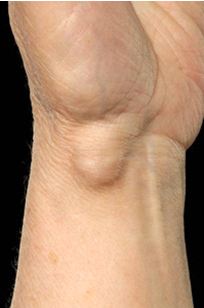

کیست گانگلیون شبیه به کیسهای مملو از مایع است که معمولاً در اطراف مفصل و غلاف تاندون دست، مچ دست یا پا ظاهر میشود. کیست گانگلیون شایعترین تومور (توده) بافت نرم در دست و مچ دست است که میزان شیوع آن در زنان نسبت به مردان 3 به 1 میباشد. ممکن است این نوع کیست در هر سنی اتفاق بیافتد. به نظر نمیرسد که هیچگونه ارتباطی میان بروز کیست و انجام کارهای دستی و شغل فرد وجود داشته باشد. زمانی که کیست دست موجب بروز ناراحتی شود یا فعالیت فرد و دامنه حرکتی وی را تحت تأثیر قرار دهد، چندین گزینه درمانی قطعی برای رفع آن وجود دارد. یکی از روشها این است که پزشک ترجیح میدهد فقط ناحیه دارای کیست برای مثال مچ یا انگشتان دست را درون آتل قرار دهد. همچنین ممکن است پزشک جهت کمک به کاهش درد، مصرف داروهای ضدالتهاب نظیر آسپرین یا ایبوپروفن را تجویز کند.

این نوع کیستها دقیقاً در زیر ناخن ایجاد میشوند و از آخرین مفصل انگشتان نشاءت میگیرند و به وجود آمدن این نوع کیست نیز با تخریب مفصل مرتبط است. این کیستها به علت واردکردن فشار بر روی بستر ناخن، موجب بروز شیاری در ناخن انگشتان دست میشوند. با وارد شدن ضربه به کیست مخاطی، معمولاً مایع درون کیست ممکن است به شکل مایع ژله مانند شفافی تخلیه شود. طیف وسیعی از انواع کیست به شکل یک برآمدگی کوچک بدون درد با اندازهی 1 تا 3 سانتیمتر به وجود میآیند. بعضی از کیستها دارای حالت کشسان و محکم هستند و جابجا میشوند. گاهی این کیستها دارای علائم و نشانههای یک بیماری هستند. علائم شایعترین علائم این کیستها عبارتند از:

توجه بهظاهر و محل کیست معمولاً برای تشخیص کیست گانگلیون کافی میباشد. علاوه بر این در هنگام معاینه جسمی بهوسیله چراغقوه بر روی کیست نور انداخته میشود. ممکن است پزشک جهت تائید تشخیص خود از مایع درون کیست نمونهبرداری کند. عکسبرداری اشعه ایکس غالباً در مواردی استفاده میشود که پزشک به وجود مشکلاتی نظیر استئوآرتریت (ورم مفاصل و استخوانها)، خارهای استخوانی، تومورهای استخوانی یا انواع شکستگی مشکوک باشد. بااینحال میتوان از عکسبرداری اشعه ایکس جهت تشخیص آسیبهای واردشده به استخوان مچ دست براثر کیست استفاده نمود.